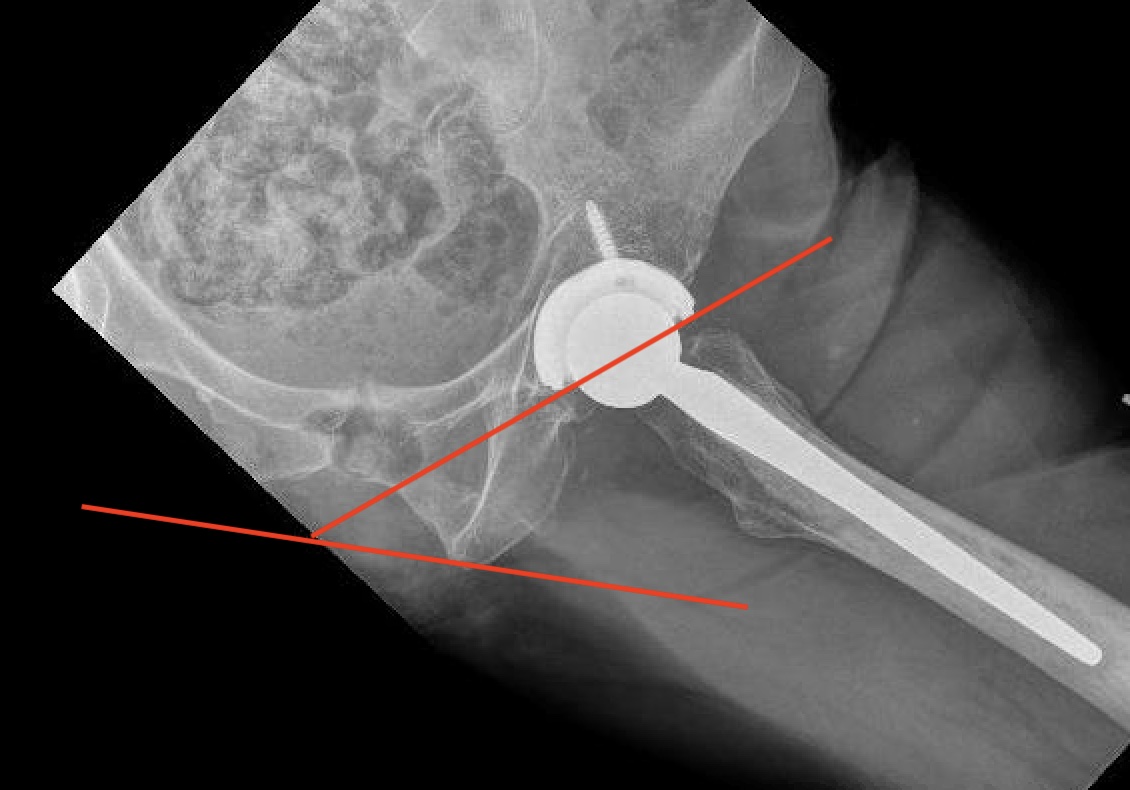

3. Femoral Version

CT scan

- line prosthesis neck

- line posterior femoral condyles

4. Offset

Xray

- difficult to evaluate on xray

- affected by femoral anteversion